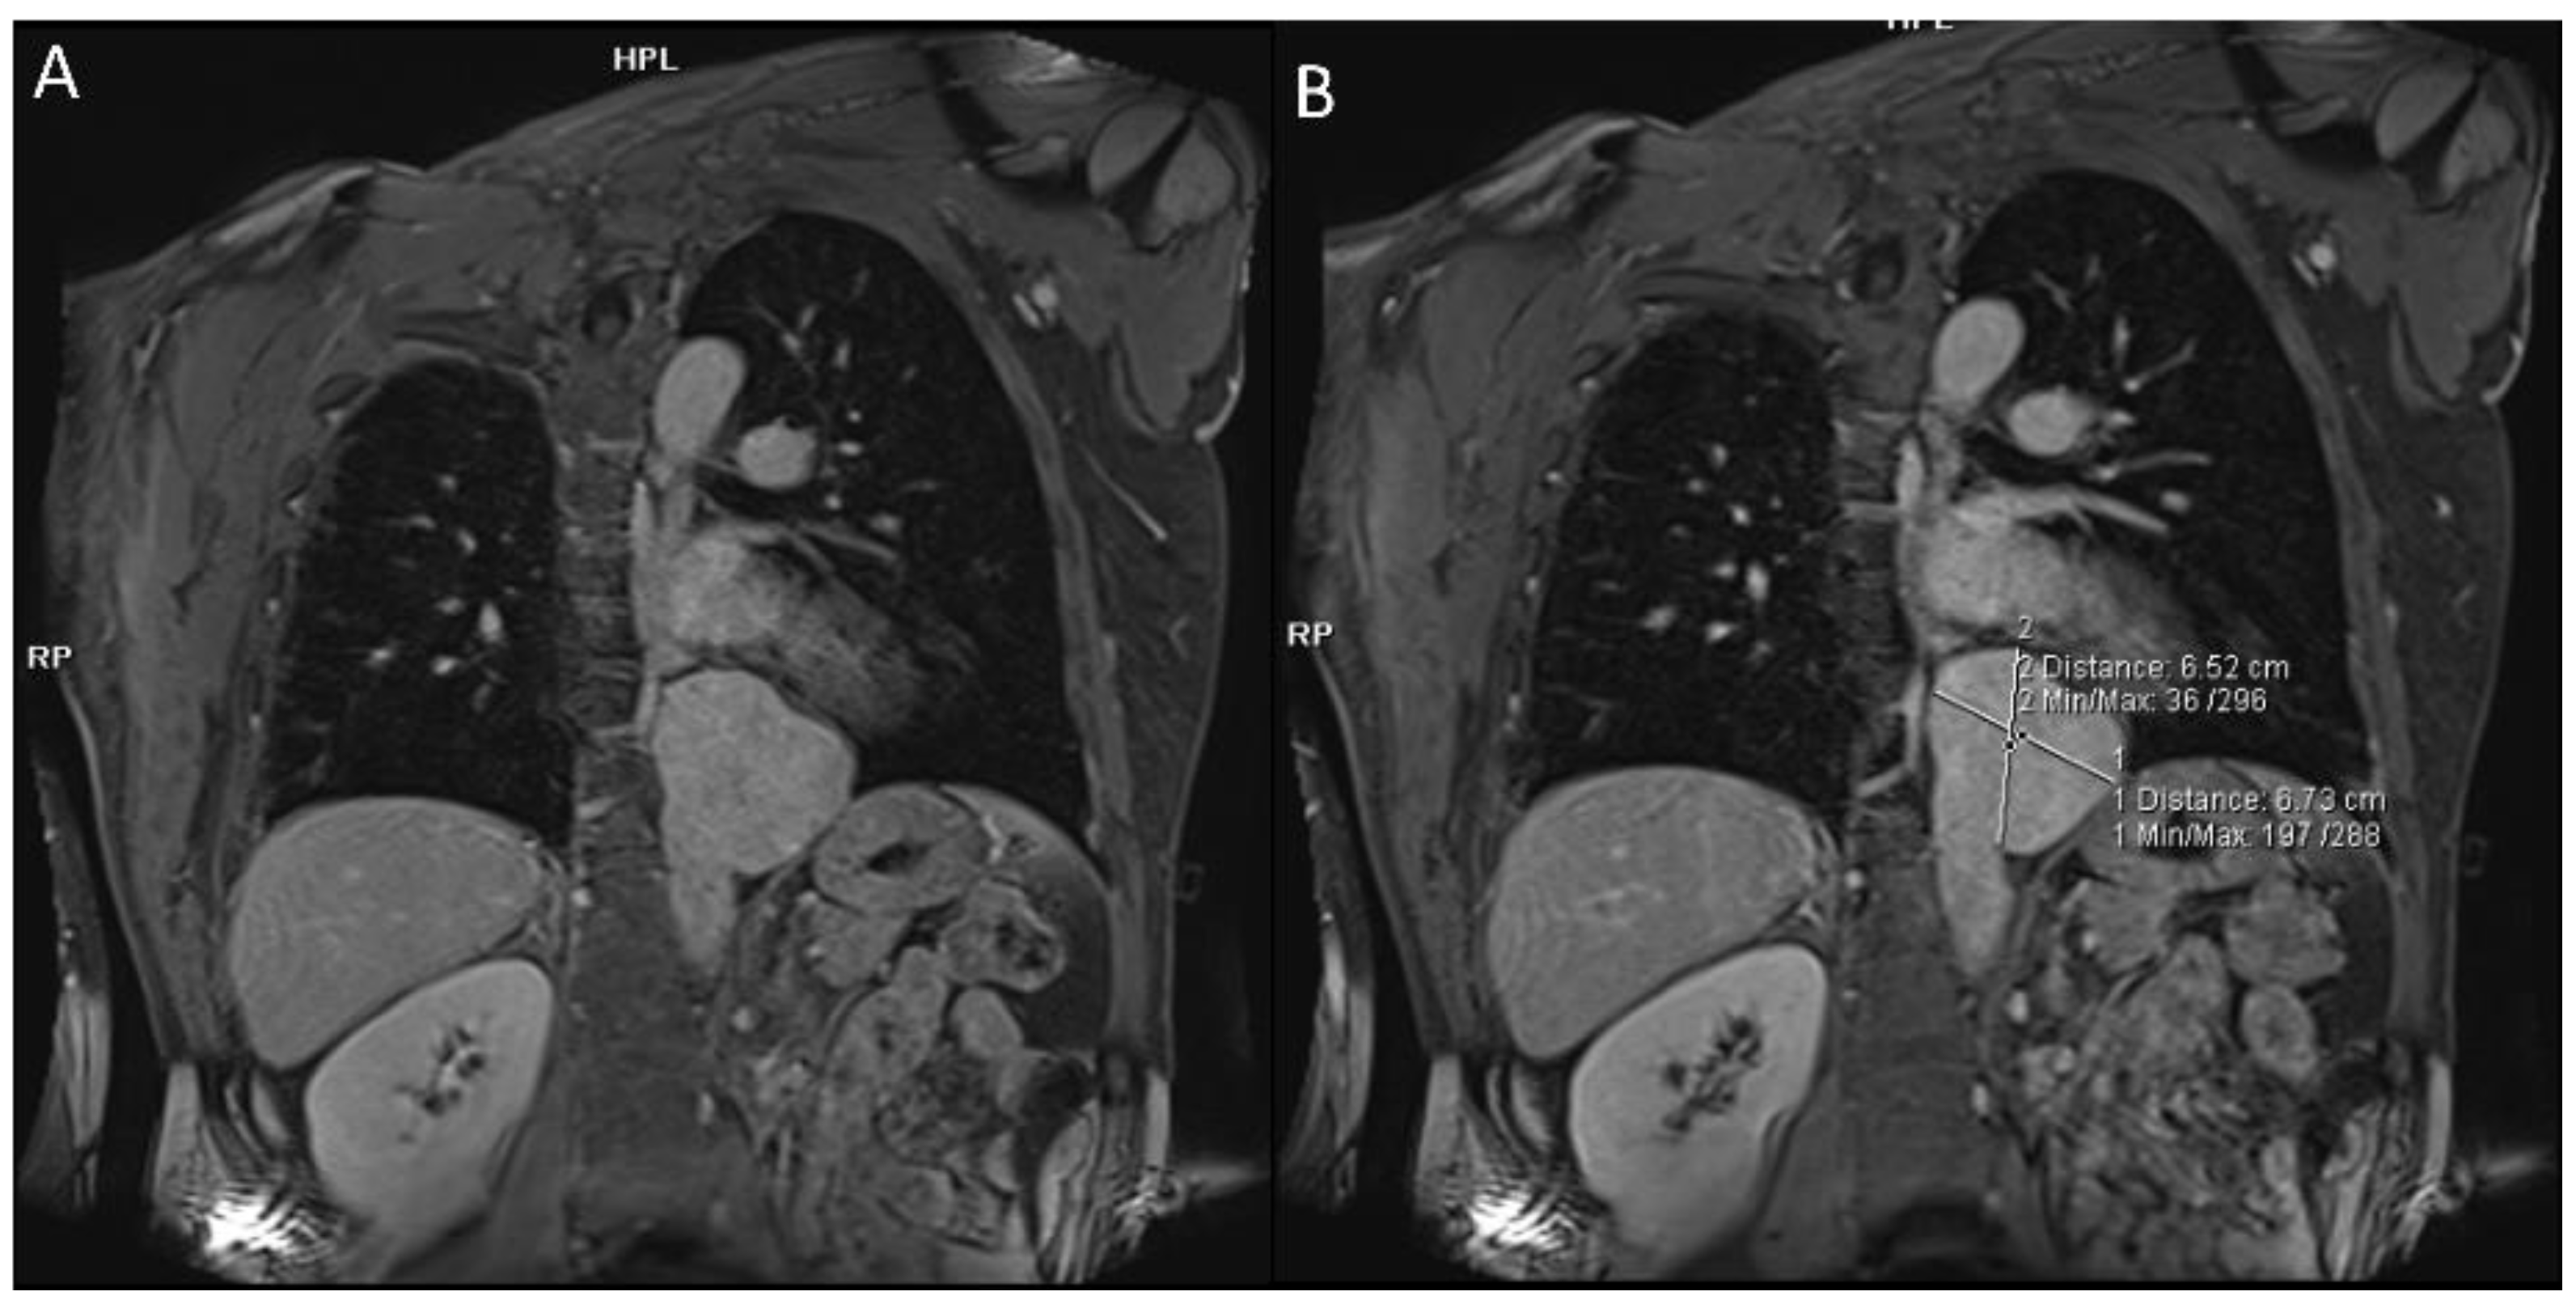

2.1.2. Pulmonary Arterial Manifestations

2.1.3. Systemic Veins

2.3. Mediastinum and Heart